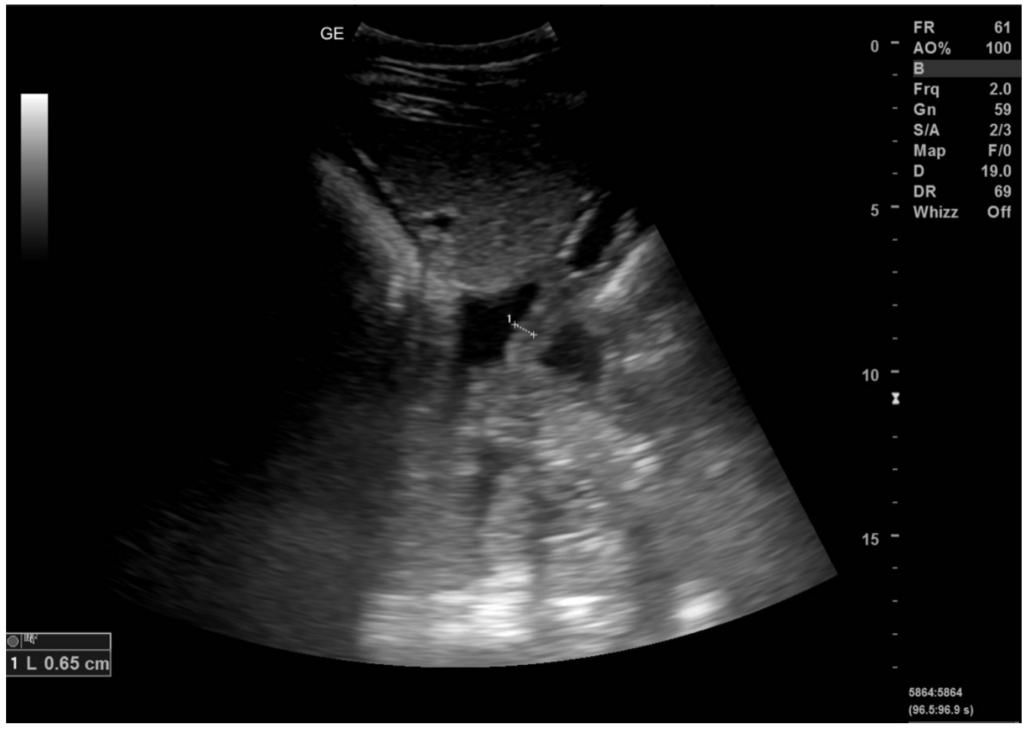

Image Right displacement of ascending colon, horse MSD Veterinary Manual What Causes A Twisted Bowel In Horses The most serious causes of colic are displacement colic, volvulus (twisted gut), or intestinal disorders. Some parts of the horse’s intestines are mobile and in some conditions can. Learn about the various causes of colic in horses, such as impactions, gas, twists, enteroliths, and inflammatory conditions. Recognize the signs of colic and how to prevent and. Twisted gut, a serious. What Causes A Twisted Bowel In Horses.

ImageCecum and right colon, horseMSD Veterinary Manual What Causes A Twisted Bowel In Horses Typically instigated by colic, or acting as a response to it, the manifestation of this condition often leads to horses rolling excessively, thereby exacerbating the situation. Recognize the signs of colic and how to prevent and. A twisted gut, a painful condition for a horse, typically causes rapid heart rate and breathing, red or grayish gums, distended. Learn about the. What Causes A Twisted Bowel In Horses.